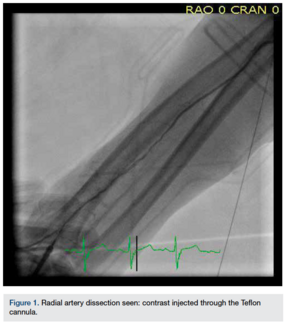

Matthew Cholankeril, MD; Kintur Sanghvi, MD, FACC, FSCAI

Even though it is rare, radial artery access can be complicated by radial artery dissection, perforation, or radial artery occlusion.